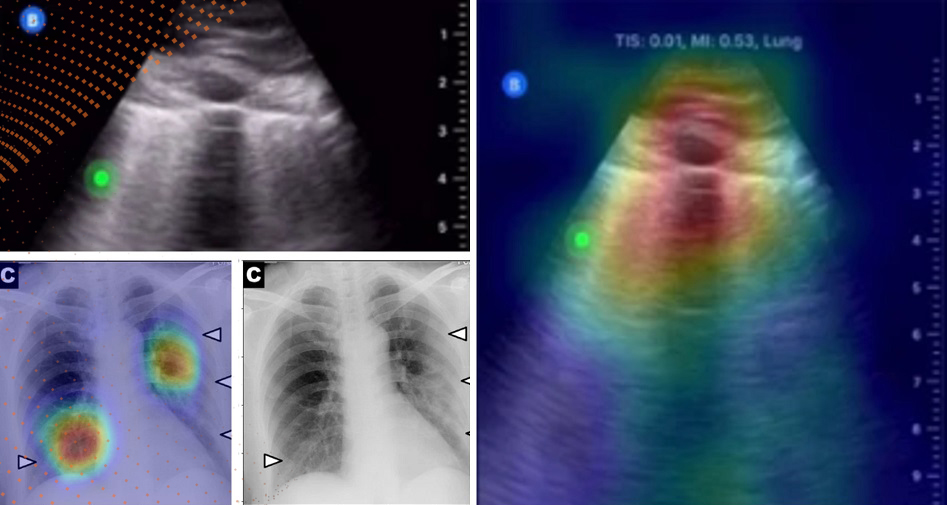

Une recherche supervisée par Moulay Akhloufi, professeur au Département d’informatique et directeur du groupe de recherche PRIME, a permis de développer une première solution permettant le dépistage de la COVID-19 sur des radiographies pulmonaires. Une collaboration avec l’Institut du Savoir Montfort a ensuite permis de tester et d’améliorer cette solution. Le professeur Akhloufi a d’ailleurs reçu une subvention du Conseil de recherches en sciences naturelles et en génie du Canada pour poursuivre sa recherche.